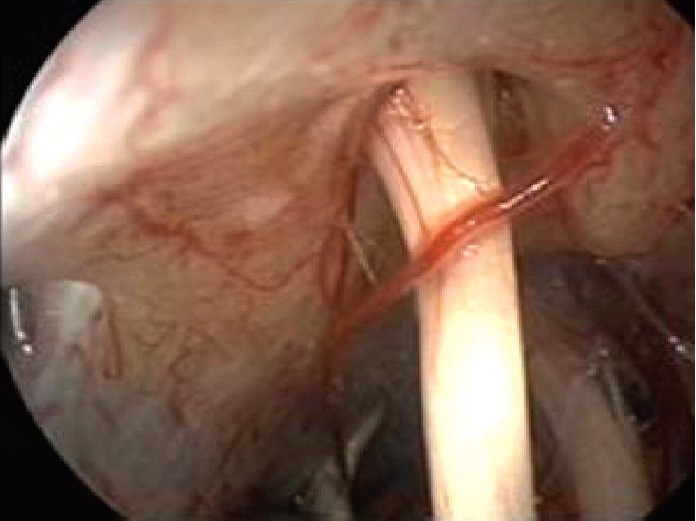

Cerrahi: Tıbbi tedavi istenen sonuca ulaşılamamış ise ameliyat yapılabilir. Vestibüler siniri sıkıştıran bir vasküler lup (katlanma – sıkışma yapan kısım) mikrovasküler dekompresyon adı verilen işlem ile sinire yansıyan baskı ortadan kaldırılabilir. Uzman ellerde minimal morbidite ile endoskopik olarak yapılabilir.